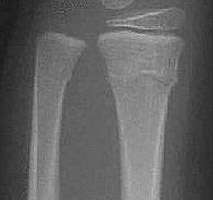

Also known as a buckle fracture. This is a compression fracture of a long bone, typically in children. This type of fracture usually occurs near the metaphysis. Both cortical margins are affected, but a discreet fracture line or trabecular disruption is not present. Minimal buckling of the cortex is present.

- Click on the image for a larger versionAAP radiograph of the forearm. The typical appearance of a torus fracture with buckling of the cortical surface.